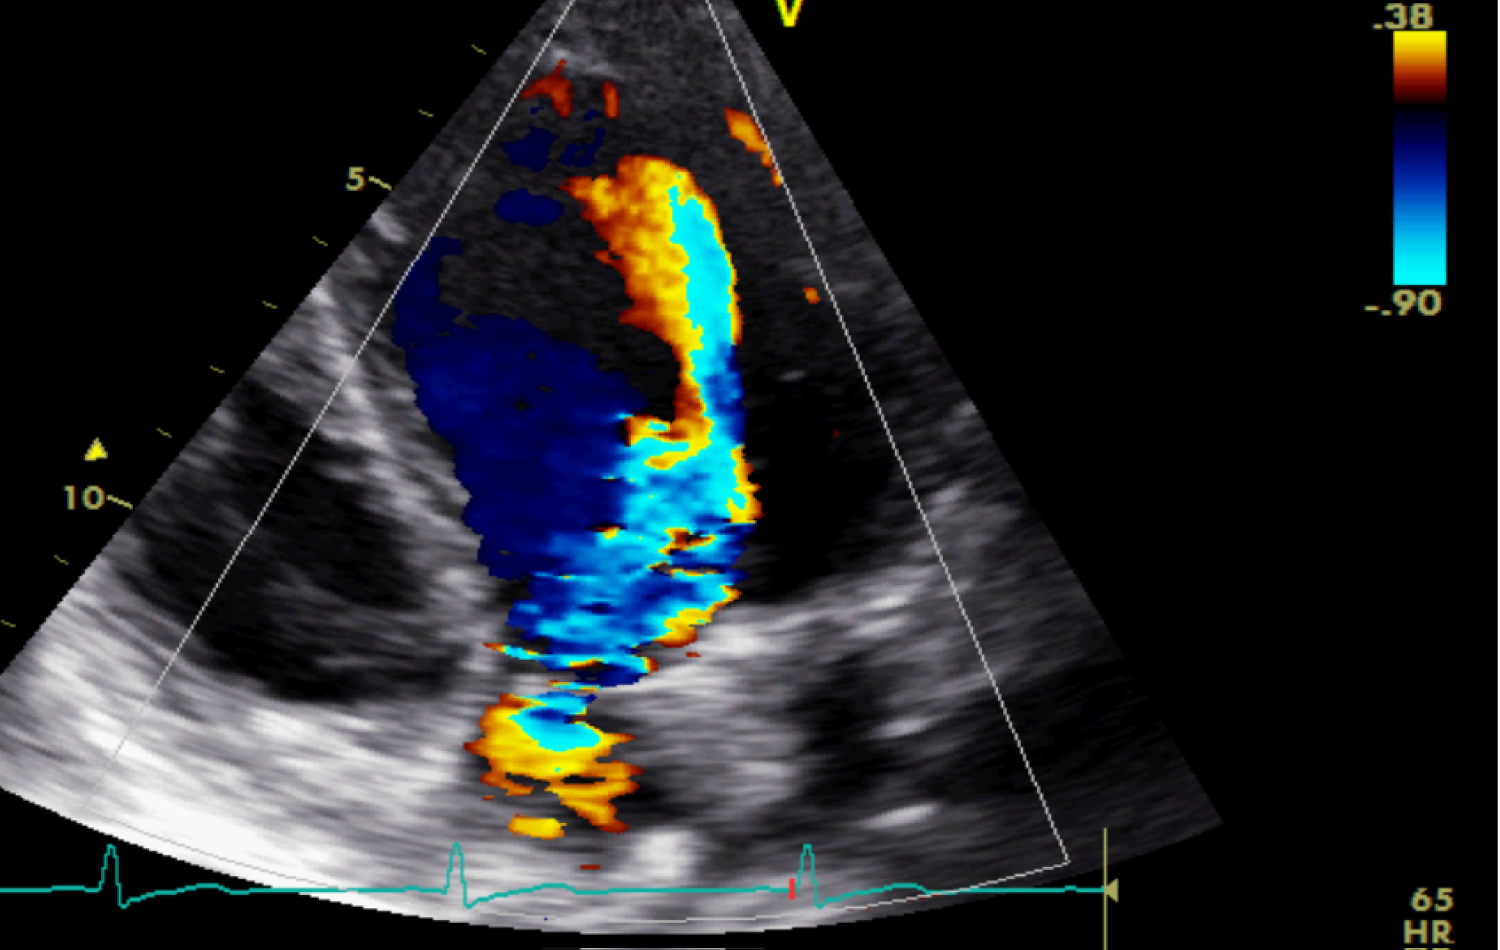

Transthoracic echocardiography revealed a significantly enlarged left ventricule with LVEDD at 53 mm (Z score 2,6), with preserved systolic function. Trileaflet aortic valve was thickened, with a severe aortic insufficiency (ERO = 50 mm2, Rpisa = 9 mm, PHT = 170 ms, TDE = 23 cm/s,), without stenosis. No signs of infective endocarditis were present. A competent mitral valve. No pericardial effusion was noted. The ascending aorta was morphologically normal (Figure 1 and Figure 2).

Figure 1: Apical five chambers view revealing a severe aortic regurgitation. View Figure 1